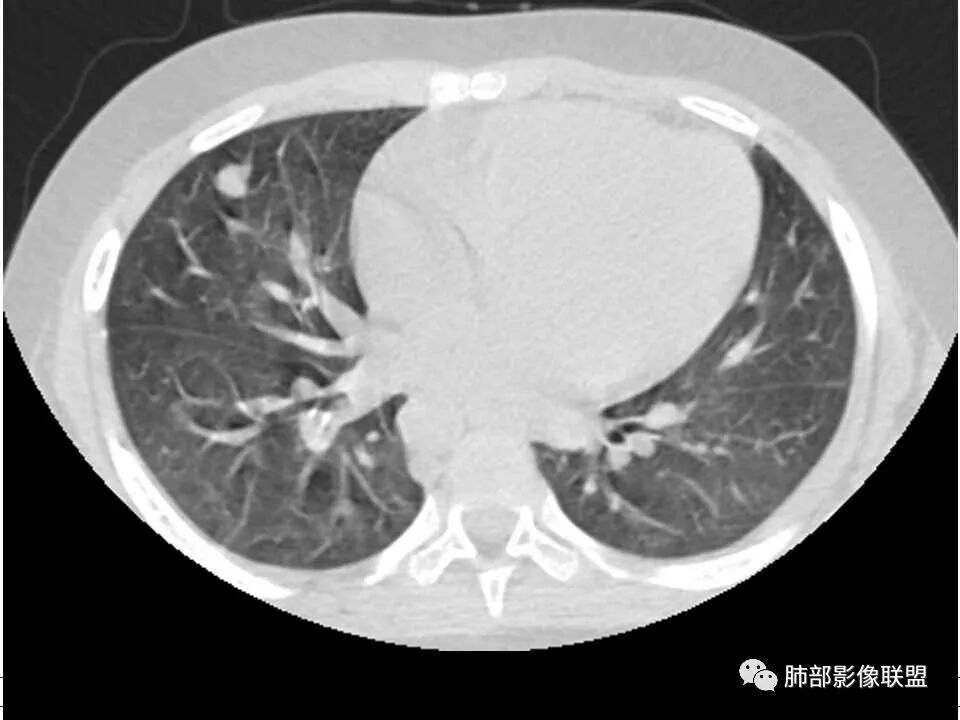

晨读,儿童,起病急,病程短,有下肢疼痛伴肿胀病史,发热,白细胞升高,结合下肢辅查,考虑骨髓炎,胸部ct:双肺多发空洞,结节,外带下叶为主,空洞内外光滑,无丝状物,有血管滋养征,综合病史及影像考虑脓毒性肺栓塞,金葡可能性大,建议痰培养,血培养,必要时ngs。

儿童患者,右下肢肿痛、发热起病,血象升高,双肺多发结节影,右肺结节并囊腔或空洞,左肺多发实性结节以胸膜下分布为主,考虑感染性病灶,有右下肢肿胀,需考虑蜂窝织炎, 血源性肺播散,金葡感染可能性大?

双肺多发结节,空洞,与胸膜相连,血道来源,空洞内壁光滑,结节周围模糊,考虑金葡菌感染。

患者儿童,因右下肢疼痛伴肿胀14天就诊。病程中有发热及伴随症状。膝关节MRI提示右侧膝关节及右髌骨髁异常信号影,右膝髌上囊及关节腔内少量积液。胸部CT:双肺胸膜下多发结节影,部分结节空洞形成,且结节周围可见血管集束征。综合考虑血源性脓毒性肺栓塞、坏死性肺炎。右侧骨髓炎、血播性金葡菌肺炎,鉴别其他特殊感染及血管炎。

胸部ct:双肺多发空洞,结节,外带下叶为主,空洞内外光滑,有血管滋养征,综合病史及影像考虑脓毒性肺栓塞,结合病史,金葡可能性大。

小儿,急性起病,下肢疼痛,mr提示骨髓水肿,临床化验炎性指标高,考虑金葡菌骨髓炎,双肺多发结节,以血管支气管束及胸膜下分布为主,部分结节近端与血管相连,部分结节可见空腔,内壁光整,部分囊腔有张力,考虑骨髓炎并肺内血播感染,金葡?

2.双肺多发片影,随机分布,多空洞或囊腔,胸膜下多楔形影,气道未见受累等等符合脓毒血症影像学表现,尤其是金葡。